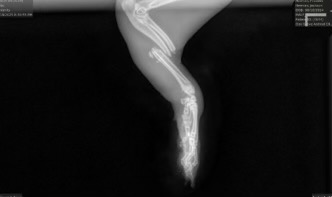

Saturday Night Basil got into an accident which resulted in her arm being broken completely in half. I am at a loss on what to do. The vet has given us two options. Euthanize my sweet girl or pay for a $10,000 operation. This includes the pre exam, the surgery itself, post op appointments, pain medications, and anti bacterial medications. I am a student at UGA and I have spent the rest of my savings on her X-rays and pain medication for the next two weeks. In this time I am hoping to raise enough money to save my sweet girl.